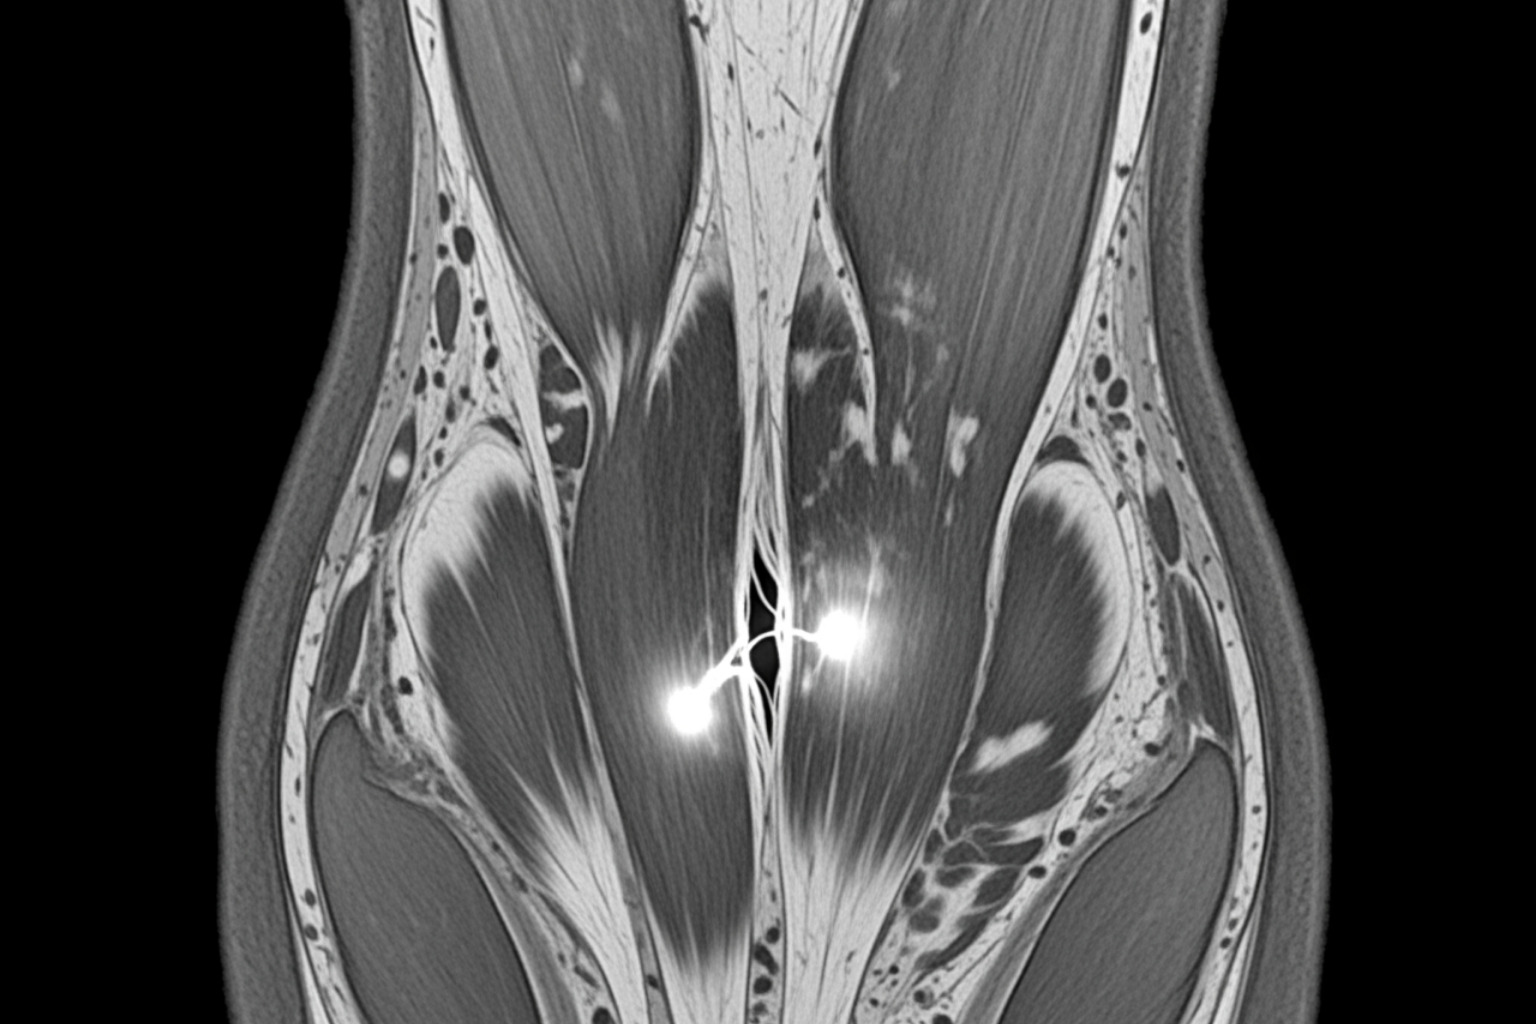

MRI scan showing a clear hamstring tear with inflammation and fluid accumulation, highlighting the injured area in detail - recovery time hamstring tear

• Central Tendon Disruption: Research highlights that injuries involving the central tendon, especially within the biceps femoris muscle, are associated with much longer recovery times. For players with central tendon injuries, recovery can range from 72 to 91 days. This is a crucial insight, as MRIs can help physicians identify such disruptions and provide a more accurate prognosis. The presence of central tendon disruption can make a seemingly moderate injury have a recovery timeline closer to that of a severe one.

We rely on thorough diagnosis, often using advanced imaging like MRI, to pinpoint the exact nature and severity of the injury. MRIs are particularly valuable for identifying central tendon disruptions or avulsion fractures that might necessitate surgery. Mayo Clinic offers more insights into diagnosis and treatment options.